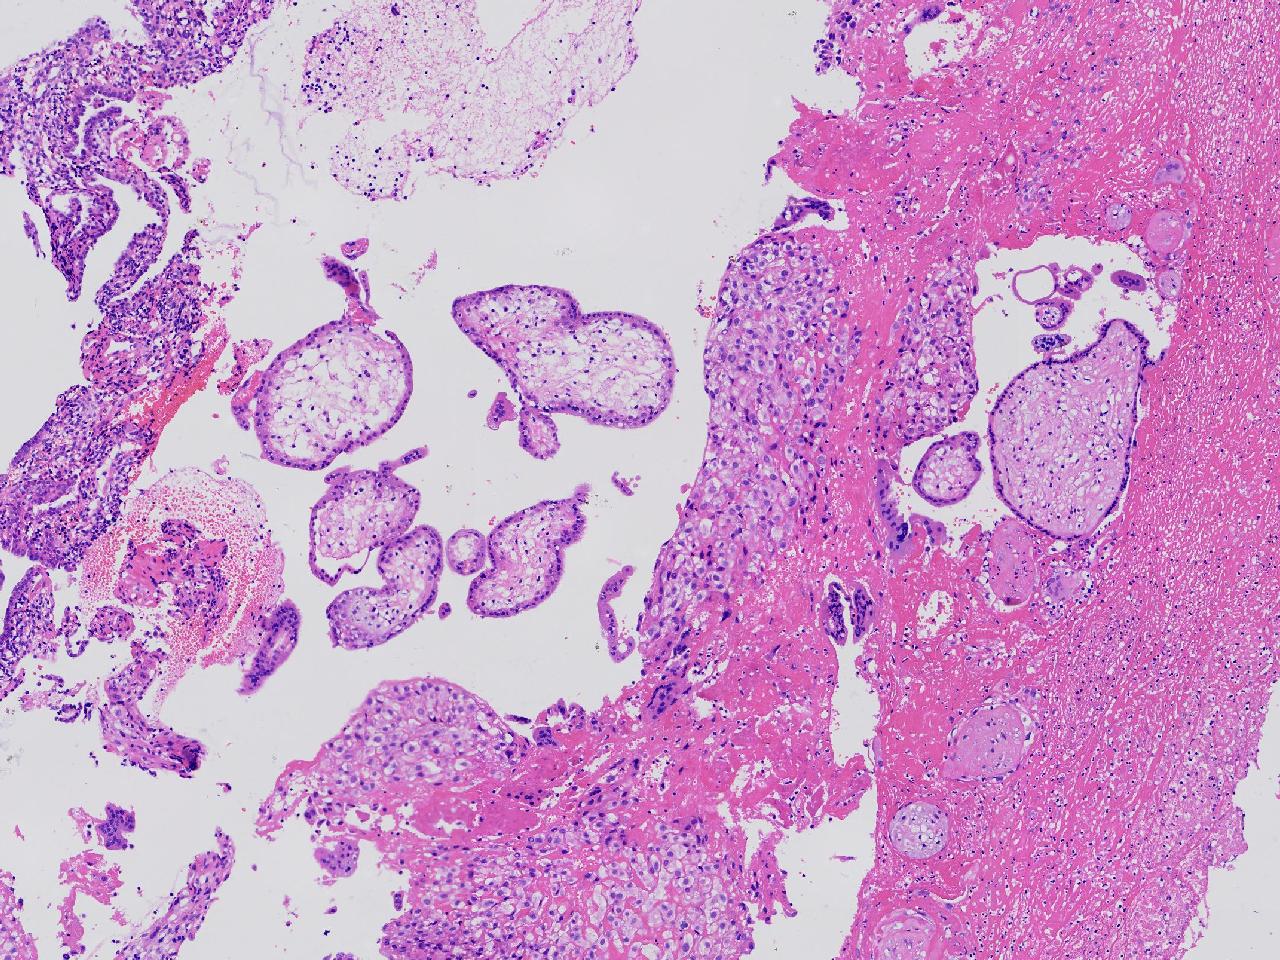

女,29岁,药物流产20余天,阴道少量出血20余天。行诊刮术。

宫腔内容物

灰粉色不整形软组织多块,4X3X3厘米,部分为血凝块。

送检组织为胎盘绒毛及蜕膜组织及滋养层细胞考虑为不全流产